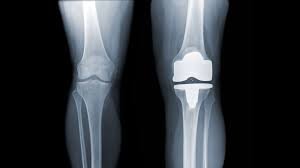

Zimmer Biomet Wins FDA Nod for Metal-Safe Knee Implant

Zimmer Biomet Secures FDA Clearance for Persona® Revision SoluTion™ Femur, Expanding Options for Metal-Sensitive Knee Implant Patients...